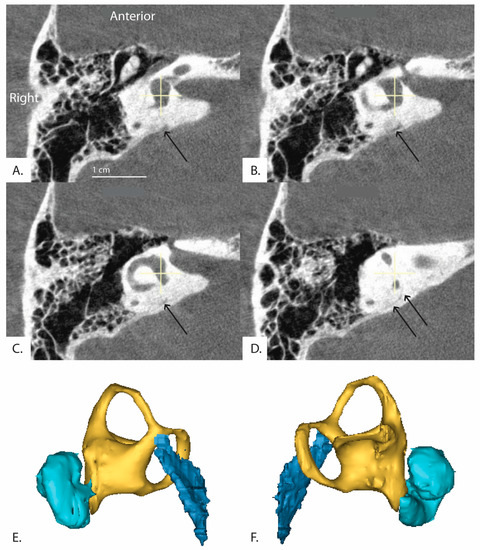

Cochlear Aqueduct Morphology in Superior Canal Dehiscence Syndrome

by Nimesh V. Nagururu, Diane Jung, Ferdinand Hui, Monica S. Pearl, John P. Carey and Bryan K. Ward

The cochlear aqueduct (CA) connects the scala tympani to the subarachnoid space and is thought to assist in pressure regulation of perilymph in normal ears, however, its role and variation in inner ear pathology, such as in superior canal dehiscence syndrome (SCDS), is [...] Read more.

The cochlear aqueduct (CA) connects the scala tympani to the subarachnoid space and is thought to assist in pressure regulation of perilymph in normal ears, however, its role and variation in inner ear pathology, such as in superior canal dehiscence syndrome (SCDS), is unknown. This retrospective radiographic investigation compared CA measurements and classification, as measured on flat-panel computerized tomography, among three groups of ears: controls, n = 64; anatomic superior canal dehiscence without symptoms (SCD), n = 28; and SCDS, n = 64. We found that in a multinomial logistic regression adjusted for age, sex, and BMI, an increase in CA length by 1 mm was associated with a lower odds for being in the SCDS group vs. control (Odds ratio 0.760 p = 0.005). Hierarchical clustering of continuous CA measures revealed a cluster with small CAs and a cluster with large CAs. Another multinomial logistic regression adjusted for the aforementioned clinical covariates showed an odds ratio of 2.97 for SCDS in the small CA cluster as compared to the large (p = 0.004). Further, no significant association was observed between SCDS symptomatology—vestibular and/or auditory symptoms—and CA structure in SCDS ears. The findings of this study lend support to the hypothesis that SCDS has a congenital etiology. Full article